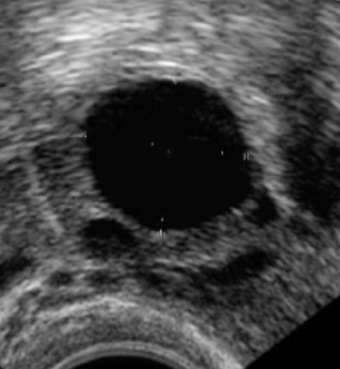

Natuurlijke cyclus

Afhankelijk van uw cycluslengte wordt enkele dagen vóór de verwachte eisprong een echoafspraak gepland in het IVF-centrum. Daarna is het afhankelijk van de groei van het ei-blaasje wanneer en of u nog een keer voor echocontrole moet komen. De controles zullen iedere één tot vier dagen plaats vinden tot het ei-blaasje groot genoeg is. Het streven is een ei-blaasje van 17 tot 18 mm. Bij deze grootte wordt de eisprong kunstmatig in gang gezet door de hCG-injectie (Ovitrelle®). De Ovitrelle® injectie zorgt ervoor dat de eisprong 38 tot 40 uur later plaatsvindt. De inseminatie wordt net voor deze periode gepland.

Figuur 2. Eierstok aan begin van de cyclus met kleine eiblaasjes en eierstok met dominant eiblaasje.